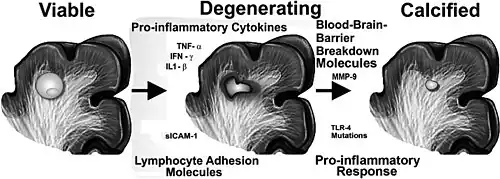

As the immune system responds to cysticerci in the brain, cysticerci go through three different stages; first becoming inflamed (colloidal stage), then breaking down (granular stage), and finally turning into hardened nodules (calcified stage). Some cysticerci remain in the viable stage for years. During the colloidal stage, the inflammation can cause damage to the brain tissue, swelling, scarring, and damage to nerve cells. In the later granular and calcified stages, swelling decreases, however scarring and clusters of immune cells in the brain (brain granulomas) may remain.[28]